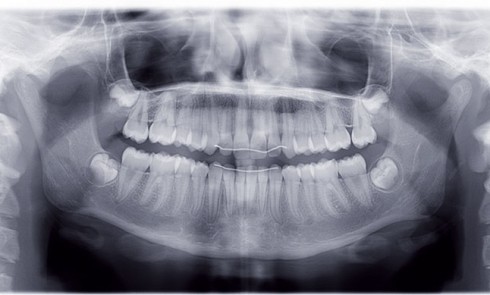

Article réservé à nos abonnés Traitement d’un cas de classe III

Cette patiente est venue consulter pour son occlusion inversée et ses importantes malpositions dentaires antérieures associées à la perte d’une...